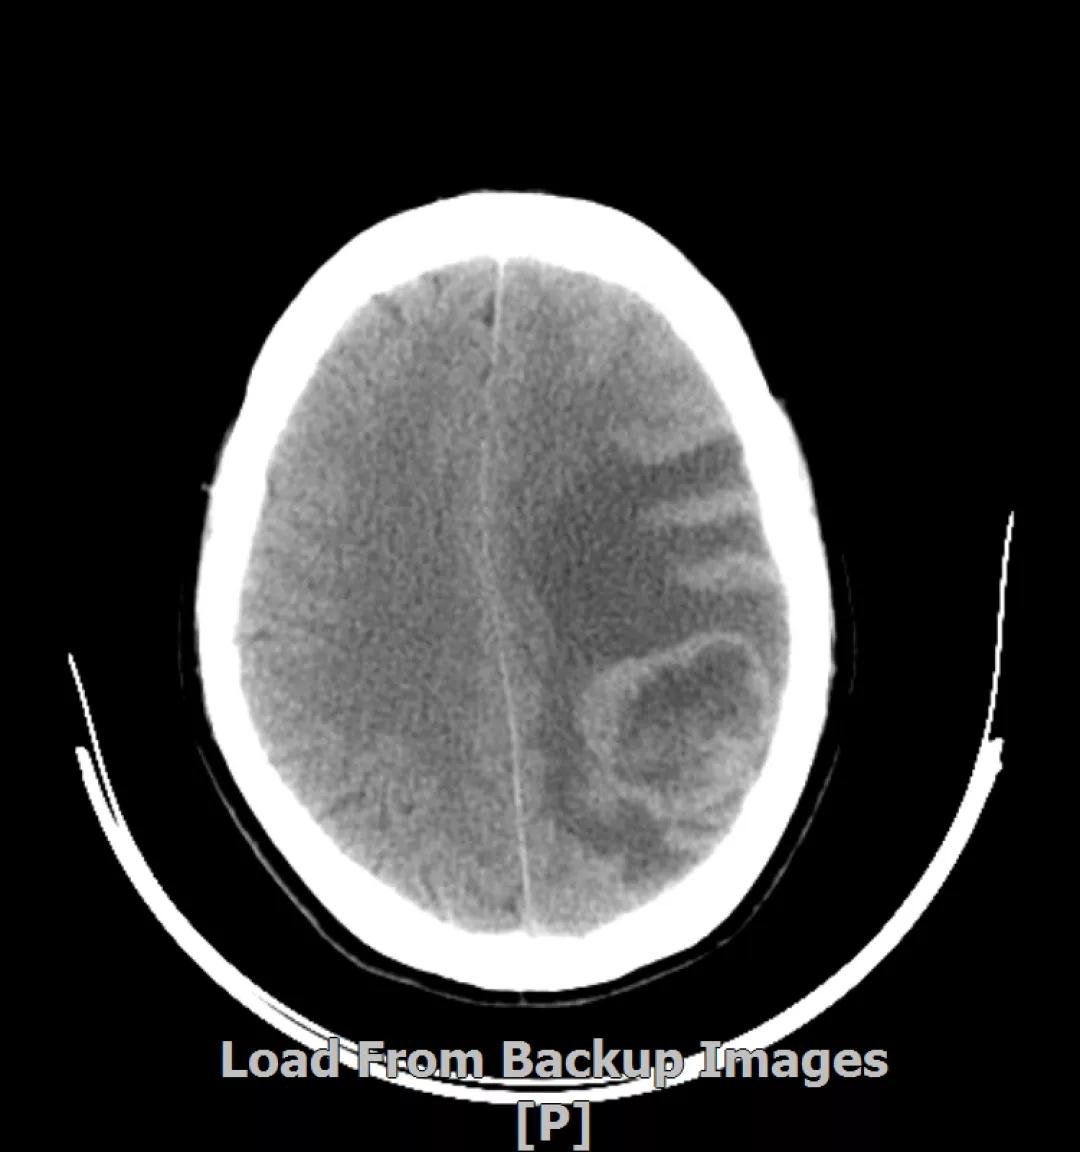

3.病情第2次进展: 2016年12月患者再次出现头痛症状

头颅增强MR:左侧顶枕叶见片状T1WI低信号、T2WI高信号影,增强后病灶边缘见局部斑片状强化改变,邻近脑膜轻度强化改变;右侧脑室三角区内侧见大小约8x14mm的结节影,T1WI低信号、T2WI等高信号,增强明显强化,灶周水肿明显;两侧脑室旁见片状异常信号,T1WI低信号,T2WI高信号,增强未见明显强化,余脑室、脑池、脑沟大小形态可,中线结构居中无移位

左顶叶脑转移瘤术后放疗后,左顶叶术区边缘强化灶;考虑肿瘤复发

右侧脑室三角区内侧转移瘤

两侧脑室旁云絮状异常信号,考虑放疗后改变

患者一线治疗的PFS为37个月。2017年1月,患者二线治疗为在原“拉帕替尼+阿那曲唑”基础上,加曲妥珠单抗治疗。患者头痛症状有所改善,病灶缩小,继续定期复查。